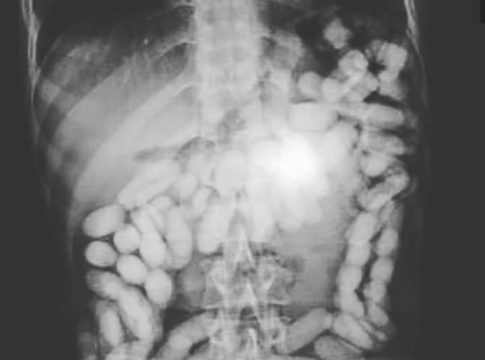

Con motivo de un control en uno de los vuelos llegado de Sudamérica, fue detenido un varón del que se pudo constatar a través del sistema de rayos X que portaba droga en su cuerpo.

Una vez detenido el viajero e ingresado en el hospital fue expulsando hasta un total de 50 cilindros con cocaína, que contenían cerca de 400 gramos. Tras el incidente, el Grupo I del Grupo de Estupefacientes, se hizo cargo de las investigaciones.